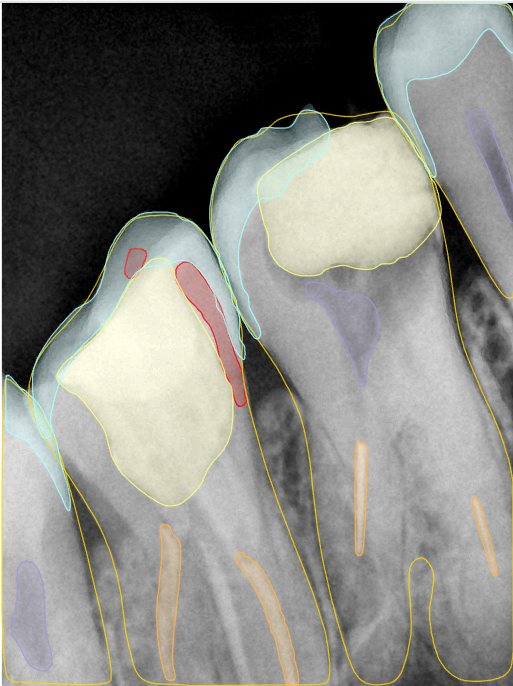

第二版算法问题测试

| 第一版 | 第二版 | 是否解决 | |

|---|---|---|---|

![]() | ![]() ![]() 边角识别有问题 龋齿识别不全 牙髓识别不全 | ![]() | 解决 |

![]() | ![]() 边角识别有问题 识别信息有误 自查(牙冠识别不全) | ![]() | 解决 |

![]() | ![]() ![]() 边角识别有误 大范围填充识别遗漏 | ![]() | 解决 |

![]() | ![]() 识别信息不全 | ![]() | 解决 |

![]() | ![]() ![]() 边角问题 牙胶识别不全 牙冠识别不全 | ![]() | 解决 |

![]() 换图片 | ![]() | ![]() 牙冠部分稍微白了一些就识别成小范围修补,部分判断异常 | 部分解决,修复类略敏感,牙冠部分稍微白了一些就识别成小范围修补,部分判断异常。 |

![]() | ![]() ![]() 牙冠识别不全 牙髓不全 根尖炎龋齿识别有误 | ![]() | 解决 |

![]() | ![]() | ![]() | 解决 |

![]() 换图片 | ![]() | ![]() | 解决 |

![]() | ![]() 牙冠识别有误 | ![]() | 解决 |

![]() 换图片 | ![]() ![]() 边角识别有误 | ![]() 修复类敏感 | 部分解决,图像过白,导致修复类判断异常。 |

![]() 换图片 | ![]() 牙冠识别不全 | ![]() 修复类敏感 | 部分解决,图像过白,导致修复类判断异常 |

结论:修复类出现了不鲁棒的情况,后续需要加入轮廓的扩充数据进行增强。